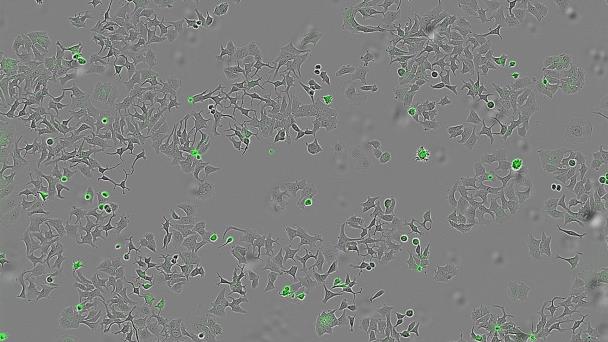

En la investigación han empleado sistemas avanzados de imagen en tiempo real que permiten contar células vivas y muertas, y medir la apoptosis (muerte programada) para observar con precisión el bloqueo de las vías.